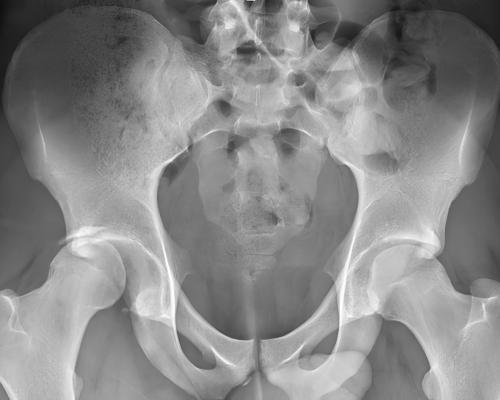

Devamını OkuProtez ameliyatları eklemdeki ilerlemiş kireçlenmelerin yol açtığı ağrı ve hareket kısıtlılığının eklem yüzlerinin metal implantlarla ( protez ) değiştirilerek eski sağlığınıza kavuşmanızı sağlayan uygulamalardır.

Devamını OkuKas-iskelet sistemi hastalıkları; kemik, eklem, kıkırdak, bağ ve kas dokularını etkileyen çok faktörlü patolojilerdir. Dejeneratif süreçler, travmalar, doğumsal anomaliler ve nöromüsküler hastalıklar bu sorunların başlıca nedenleri arasında yer alır. Tanı sürecinde klinik muayene; radyografi, manyetik rezonans görüntüleme ve gerektiğinde bilgisayarlı tomografi gibi yöntemlerle desteklenir. Ameliyatsız tedaviler; biyolojik yanıtı desteklemeyi, inflamasyonu azaltmayı ve fonksiyonel iyileşmeyi hedefler.

Protez cerrahileri, artroskopik girişimler, kırık ve deformite cerrahileri; eklem biyomekaniği, yük dağılımı ve yumuşak doku dengesi esas alınarak planlanır. Cerrahi karar sürecinde yalnızca radyolojik bulgular değil; hastanın klinik yakınmaları, fonksiyon kaybı ve yaşam kalitesine etkisi birlikte değerlendirilir. Modern ortopedik cerrahinin temel hedefi; en az invaziv yöntemle en yüksek fonksiyonel kazanımı sağlamaktır.

Kalça kireçlenmesi ( koksartroz ), kalça eklemini oluşturan femur başı ile asetabulum arasındaki kıkırdak dokunun zamanla...